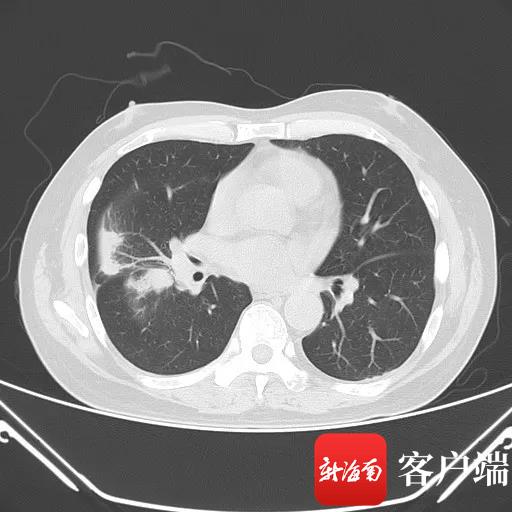

患者李先生右肺下叶肿瘤。